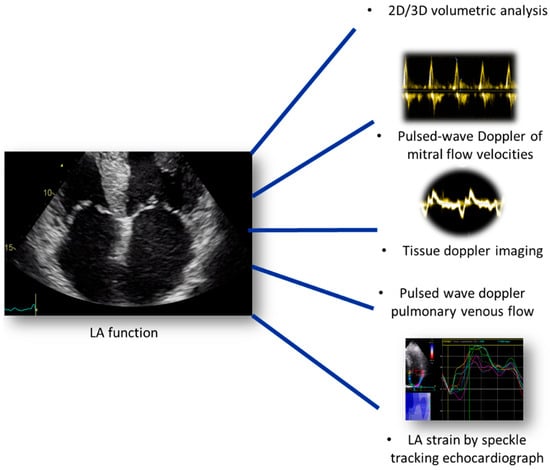

8. Assessment of Left Atrial Function

9. Left Atrial Deformation and Raised Filling Pressures